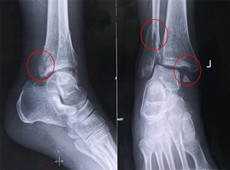

【醫療科普】踝關節骨折的主要類型及其影像學表現

大家好,我是南京醫科大學第二附屬醫院骨科副主任醫師王伯堯,從事骨科臨床工作十余年,擁有豐富的骨科臨床經驗,主要研究方向為骨科手術機器人的開發與臨床應用,今天跟大家介紹踝關節骨折的幾種常見類型及其在X影像上的表現。接下來跟...

【醫療科普】之為什么說踝關節骨折手術復雜?

大家好,我是南京醫科大學第二附屬醫院骨科副主任醫師王伯堯,為什么說醫生遇到踝關節骨折會比較“頭痛”!接下來跟普愛醫療科普小編一起來了解下吧!...